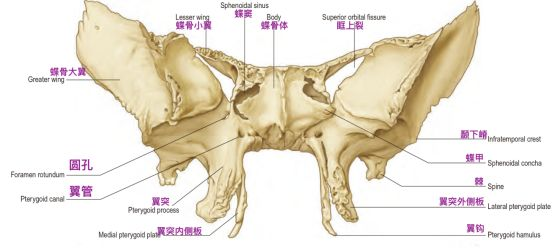

这三个孔隙的向下方穿过颅底后的开口位置是不同的。卵圆孔和棘孔均向下开口于颅底底面,而圆孔向前外侧,开口于颅骨外表面的深部间隙翼腭窝。翼腭窝后壁上的两个开口,分别是圆孔和翼管。翼管内走行翼管神经和翼管动脉。

圆孔连接中颅窝底和翼腭窝,而翼管连接翼腭窝和破裂孔。圆孔位于翼管的上、外侧。

蝶骨前面观示意图,注意圆孔和翼管的位置(Standring, 2016)。

蝶骨,前面观(Osawa 2009)。翼管位于蝶骨翼突和蝶骨体融合的交界处。翼管前方的开口位于翼突上表面上内侧部分,位于蝶窦底水平,圆孔的下内侧。